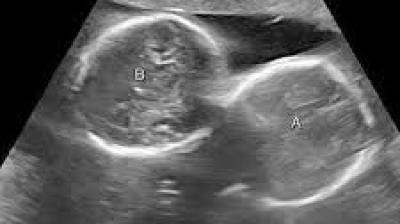

डिलीवरी के दौरान अचानक तीसरे बच्चे के जन्म से सभी चौंक गए

इंदौर। इंदौर के ESIC अस्पताल से प्रेगनेंसी का एक बेहद चौंकाने वाला मामला सामने आया है. यहां पर एक महिला ने तीन बच्चों को जन्म दिया. इससे भी ज्यादा हैरान...